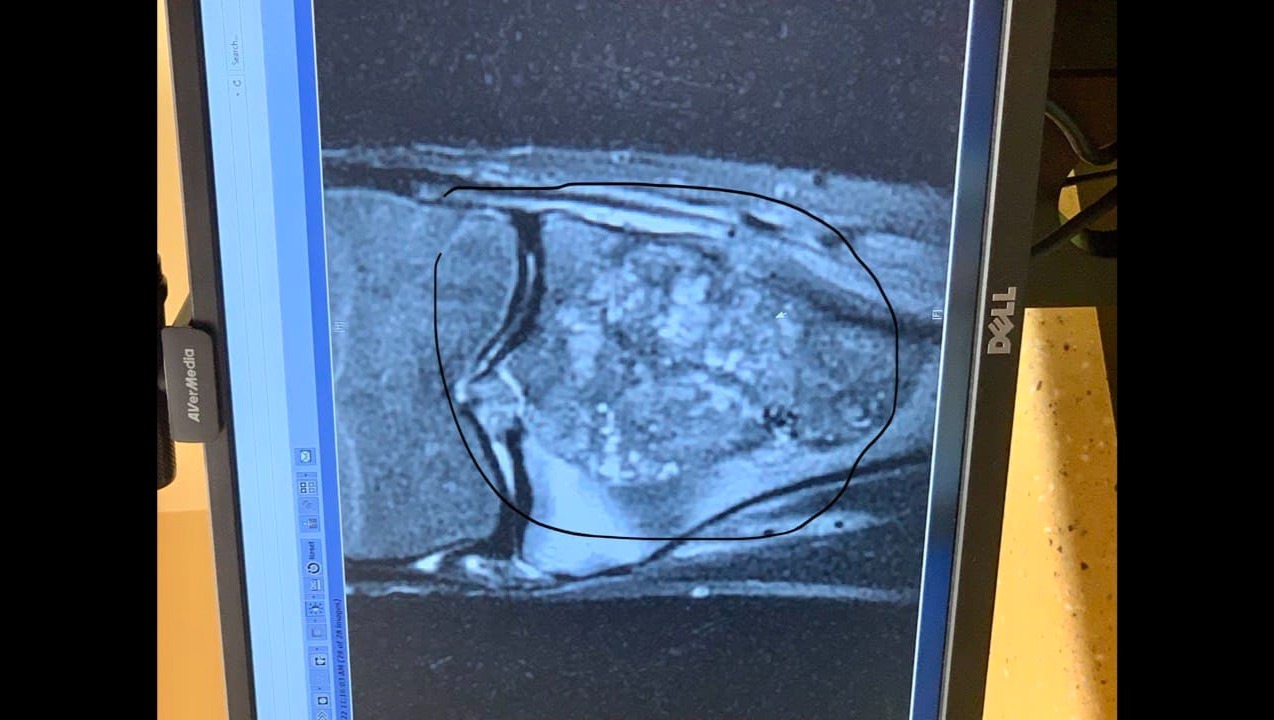

He continued to have pain and felt that a lump had developed on his knee. As the pain worsened and the lump continued to grow, his mother took him to see his family doctor. The doctor ordered x-rays, and when she saw it was a mass, she sent orders marked “URGENT” to the hospital for an MRI. In the meantime, the mass has continued to grow and is now the size of a grapefruit, is very painful and is hindering Blake from being able to walk.

On March 3, Blake underwent a biopsy to determine if it was cancer. He was diagnosed with Osteosarcoma (a rare bone cancer that is fast growing and an aggressive form of cancer), and while he was still under anesthesia, a port was put in for his chemo treatments. Then Blake will be going back to the hospital for a PET Scan and blood work next Wednesday. He will begin his first round of chemo for ten weeks.

Once his ten weeks of chemo are complete, the doctor will run tests and assess the situation. The doctor will remove the tumor and the damaged area if the chemo works. He will then do reconstructive knee surgery by cutting the bone out from where the cancer was and then putting a metal plate into part of his lower leg and under his knee to replace the removed bone.